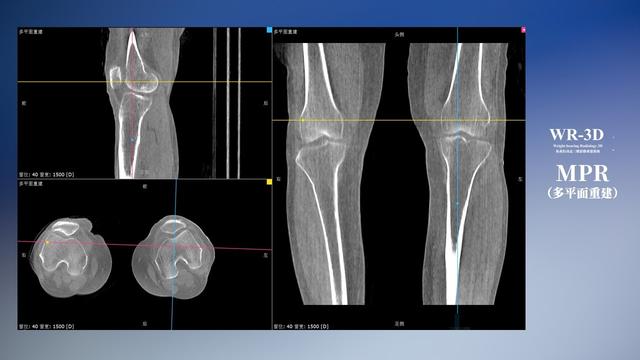

普通平片扫描与WR-3D扫描前后诊断结果对比

与此同时,数字化X线摄影技术相较于CTMRI来说,能快速获取真实、直观、满足临床需要的影像。DR的图像具有图像层次丰富、空间分辨力高、影像边缘锐利清晰、密度分辨力高级细微结构表现出色等特点,针对膝关节解剖结构数字化X线摄影技术应用价值很高,尤其是是对骨小梁与骨皮质的显示非常清楚。在负重位状态下,数字化X线三维摄影扫描与重建,能够更好的呈现受检者关节受力改变的状态。必一运动科技创新的WR-3D动态三维数字化X线摄影技术,通过数字化X线摄影完成三维扫描并重建三维影像信息,包括MPR多平面重建、MIP重建以及VR绘制。扫描时间短,剂量相较于CT设备大幅缩减,同时成本更低,在临床诊断以及医疗方案制定中具有极大的价值意义。相较于普通平片下的负重位扫描,负重位动态三维扫描摄影技术能够避免二维状态下的组织结构重叠、密度分辨率不足、组织解剖结构难以分辨等问题,WR-3D支持多角度的动态三维摄影观察,能全面的呈现被检查部位在多个角度下三维影像信息,极大的减少了二维负重位检查的漏诊率。

必一运动科技WR-3D负重位动态三维摄影技术